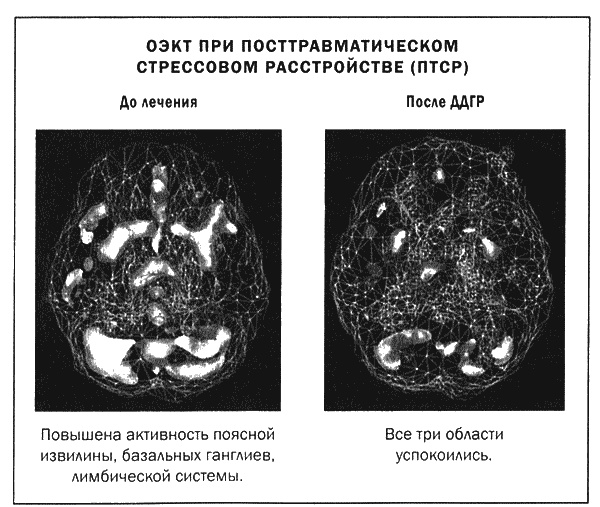

Мы проводим терапию ДДГР в Amen Clinics последние пять лет. Ею руководит психолог Дженнифер Лендл, сертифицированный тренер ДДГР, и я вижу, что эта методика очень помогает при лечении тревожности, ПТСР и для улучшения личностной эффективности пациентов. Мы изучали ДДГР с помощью методов ОЭКТ до, во время и после лечения. ДДГР действительно меняет функции мозга, поскольку успокаивает гиперактивные участки. Например, при ПТСР характерен рисунок активности мозга, который мы называем «алмазная грань»: чрезмерная активность в поясной извилине (верхняя грань алмаза), базальных ганглиях (боковые грани алмаза) и лимбической системе, таламусе (нижние грани алмаза). При таком рисунке активности мозга люди страдают от ночных кошмаров, пугливости, тревожности, беспокойства и видят мир через черные очки. Терапия ДДГР успокаивает все «грани алмаза», что доказано сканами ОЭКТ. Вот два случая из нашей практики.

Лесли было 23 года, когда она пришла на прием. В прошлом она дважды пережила изнасилования — в возрасте 15 и 22 лет, череду неуспешных любовных взаимоотношений и раннюю смерть матери (в свои 13 лет). Ее симптомами были кошмары, тревожность, депрессия и беспокойство. Скан показал типичный рисунок «алмазная грань». За четыре сессии ДДГР Лесли почувствовала себя значительно лучше. При повторной томографии выяснилось, что активность в базальных ганглиях, поясной извилине и лимбической системе снизилась.